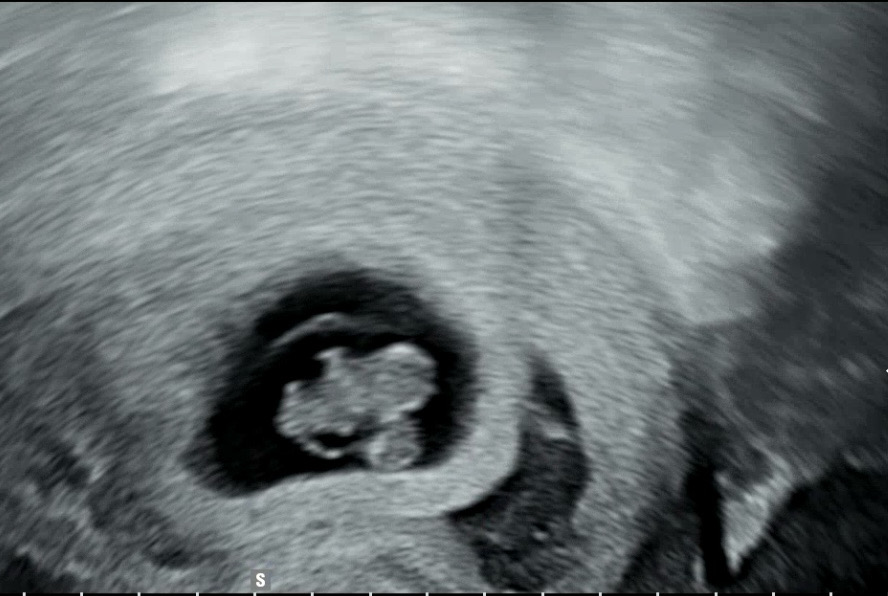

7주 6일차 갑자기 피고임

아무런 이슈가 없다가 갑자기 피덩어리가 툭떨어져서 가보니 피고임이 생겼네요ㅠ 의사선생님은 아이한테 영향없을거라 괜찮다고 하셨는데.. 저같은분 계신가요 무섭네여ㅠ